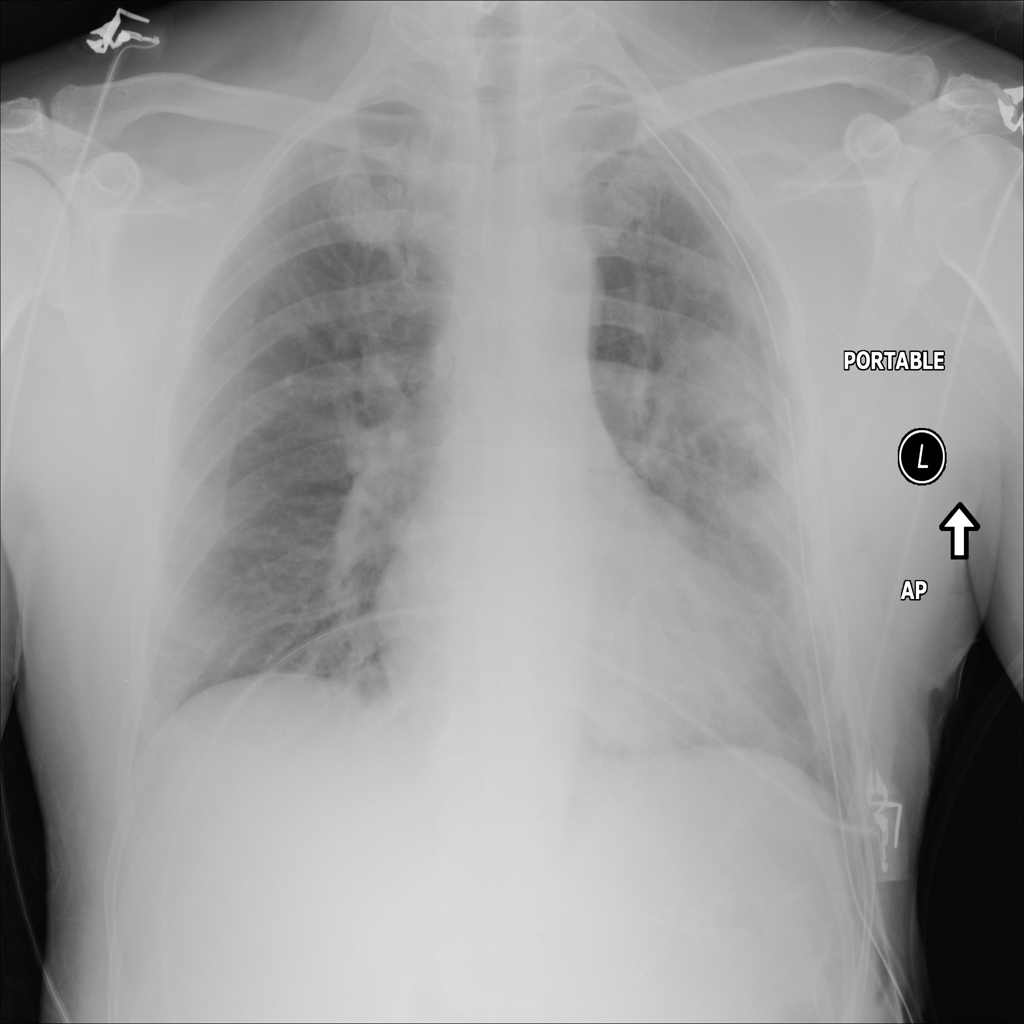

Mass

A mass is a larger focal opacity or lesion seen on the image. It is a descriptive finding that can have several causes and usually needs more imaging or clinical context to characterize.

PAT-50E5 · IMG-008Mass

PAT-50E5 · IMG-008

PA